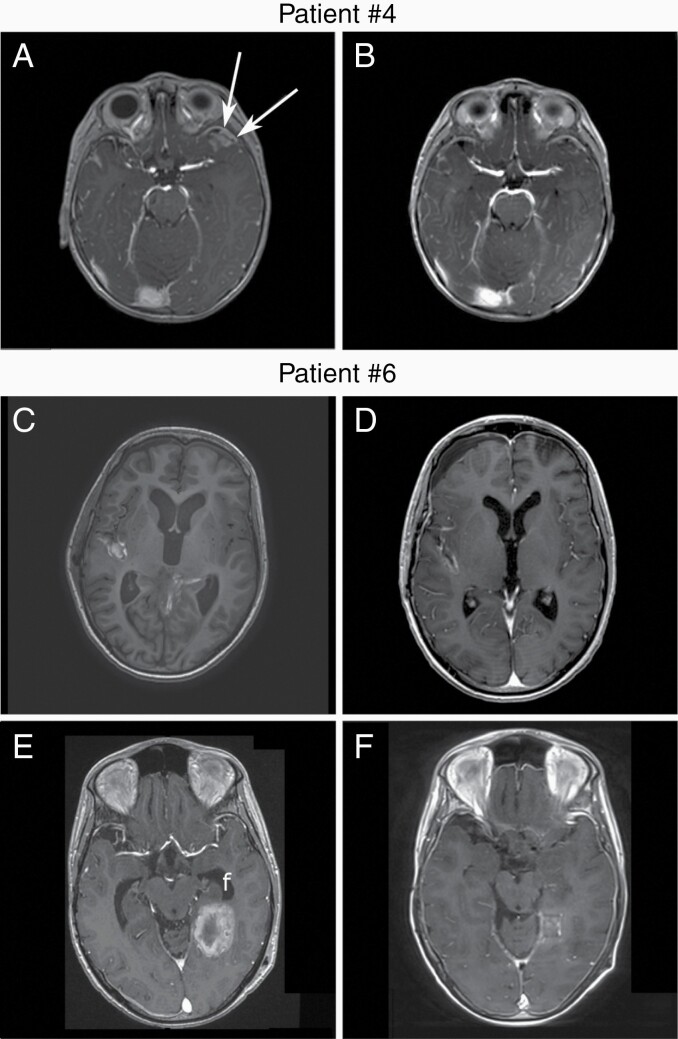

The SMOi vismodegib or sonidegib were used for 3 and 5 patients, respectively (Figure 1a). Median age at SMOi initiation was 11.1 years (range 3.3–25.5). Treatment duration was of 1.2–9.4 months, with a median duration of 7 months. All 5 patients with a known PTCH1 mutation responded to a SMOi. Patient #5 responded while no information of PTCH1 status is available. There were 6 (75%) objective responses, 4 partial remission (PR), and 2 complete remission (CR) (Figure 2, Supplementary Figure 1 and Table 1).

Figure 2.

SMOi response evaluation by MRI T1 with contrast enhancement. Patient #4 baseline MRI before SMOi initiation. Contrast enhancement of a relapse in the temporal lobe (a) showing a very good partial response after 8 weeks of sonidegib (b). Patient #6 baseline MRI before SMOi initiation showing a metastatic relapse in the Silvius fissure (c). Partial response was achieved after 2 months of vismodegib (d). A Dramatic relapse occurred while treated by sonidegib, with new metastasis in the temporal lobe (e). Partial response was achieved gain 4 months later with a combination of sonidegib and temozolomide (f). Importantly, the patient had previously received temozolomide. MRI, magnetic resonance imaging; SMOi, smoothened inhibitor.

Three patients had new attempts of SMOi treatment (#5, #6, and #7). The 2 patients for whom a combination of SMOi with other treatment, surgery, radiotherapy, or chemotherapy, had prolonged responses and several rechallenge of SMOi. Patient #6 had a PR with vismodegib during 8.8 months (Figure 2c and d) and after discontinuation for myalgia, a SMOi was rechallenged with sonidegib, with an initial and short clinical improvement quickly followed by a dramatic progression (Figure 2e). A combination of vismodegib and temozolomide was given with a very good PR, despite the fact that the patient already received temozolomide previously (Table 2 and Figure 2f). This response lasted for 11.3 months before a new PD. Among other conventional therapies, the GLI1 inhibitor, arsenic trioxide which inhibit SHH pathway downstream of SMO, was introduced without success. Finally, vismodegib was rechallenge in association with ribociclib without any response.